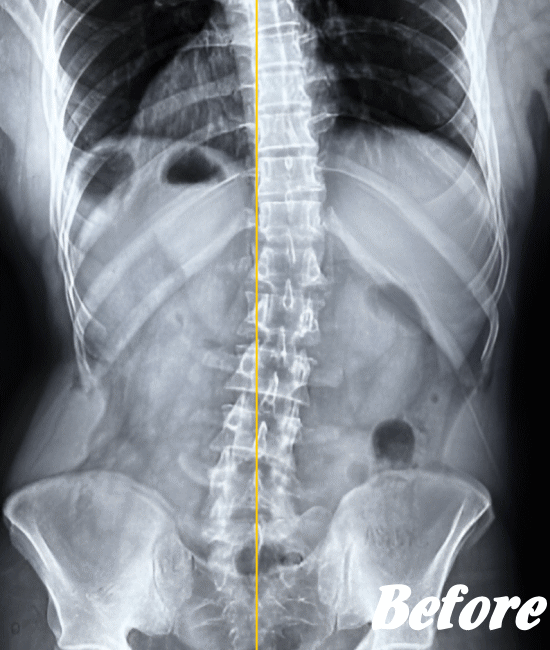

レントゲン、CT、MRIといった画像診断などで坐骨神経痛の原因となる病気(例えば、ヘルニアや脊柱管狭窄症など)が見つかれば、その治療を行います。原因となる病気が見つからない場合は、第一選択肢として、保存療法が適応されます。

HALOカイロプラクティック☆平和島整体院では、仙腸関節や腰、股関節などの部位を解剖学的に正しい状態へ戻すことで、筋肉をゆるめ、関節の詰まりを広げ、圧迫されてしまった神経を解放し、痛みや痺れのない状態へと回復させます。

また、首(頚椎)の歪みにより腰に負担がかかることで坐骨神経痛を発症することもあるため、首も調整します。

ただし、歩行に支障をきたすような激しい痛みの場合は、「股関節のズレが酷い」「腰椎の椎間が詰まっている」「ヘルニアが突出している」「仙腸関節が炎症を起こしている」…等々、通常よりも症状が悪化しているため施術回数が長引くことをご理解いただいたうえで、当院へお越し下さい。